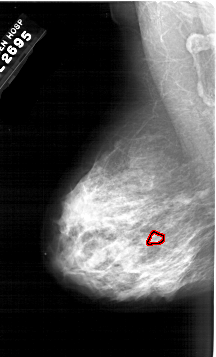

A_1983_1.RIGHT_MLO

LEFT_MLO LINES 6421 PIXELS_PER_LINE 3886 BITS_PER_PIXEL 12 RESOLUTION 43.5 OVERLAY

FILE: A_1983_1.LEFT_MLO.OVERLAY

TOTAL_ABNORMALITIES 1

ABNORMALITY 1

LESION_TYPE CALCIFICATION TYPE PUNCTATE DISTRIBUTION CLUSTERED

ASSESSMENT 4

SUBTLETY 1

PATHOLOGY MALIGNANT

TOTAL_OUTLINES 1

BOUNDARY